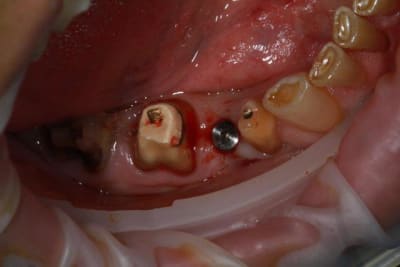

Nouveau patient, pose d'un implant il y a 2 mois....échec sans raisons particulières, douleurs et dépose.

Ce matin repose d'un nouvel implant et comme je ne veux pas prendre de risque, et que les dents adjacentes doivent être couronnées, je pose un bridge en emax press, mais scellé au ciment provisoire...

Si l'implant va bien le bridge sera déposé, coupé, et 44/46 seront collées définitivement après traitement acide et silane.

Si par hasard l'implant pose problème, dépose et bridge collé.

alors là pas du tout, le patient vient me voir pour des implants, donc je fais une étude du cas absence des molaires supérieures, couronnes mandibulaires très ancienne 45 racine cassée, 44 dévitalisée mais passablement déchaussée, donc avulsion de 45 et pose d'un implant avant de refaire les couronnes 46/47 et l'ensemble.

Échec implantaire, et oui ça arrive, même dans un cas paraissant simple.

Dépose gratuite bien sur et repose gratuite aussi, le bridge n'est pas facturé non plus, il le sera sous forme de 2 couronnes que cette fois ci l'implant fonctionne ce que j’espère, ou laissé en bridge si l'implant devait être retiré.

Le fait de scellé au ciment temporaire ne pose en principe pas de problème pour 3 à 6 mois.